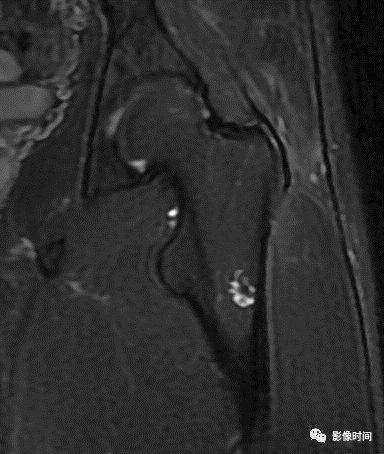

肿瘤对骨骺板和关节软骨的破坏是对骨破坏的继续。缺乏血管的骨骺板对恶性肿瘤有抵抗作用,骨骺板可暂时阻止肿瘤的蔓延,但当肿瘤进一步发展时, 骨骺板亦可被破坏,X 线平片或 CT 可表现为先期钙化带密度减低、中断或消失。MRI 可显示肿瘤从干骺端跨越骨骺板侵犯骨骺(图 15、图 16)。

图 15  骨骺板破坏:骨肉瘤

图 16  骨骺板破坏:骨肉瘤